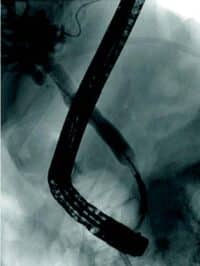

Obstruksjon av gallegang

Inflammasjon og fibrose i caput av pankreas kan skade gallegang og føre til benigne strikturer og kolestase. Slike strikturer kan være krevende å behandle. Det er viktig med god bildediagnostikk i forkant av terapi for å utelukke malign striktur, noe som kan være vanskelig på grunn av de inflammatoriske/fibrotiske forandringene sekundært til kronisk pankreatitt. Det er svært viktig at man ikke intervenerer endoskopisk dersom usikkerhet om malign etiologi men henviser til senter med HPB kirurg og MDT vurdering. Standard behandling av benigne strikturer har vært ERCP med gjentatte dilatasjoner og innleggelse av multiple plaststenter i gallegang over en periode på ett år (Fig 5). De senere år har bruk av selvekspanderende metallstent i 6-12 mnd. blitt mer vanlig dersom forholdene teknisk ligger til rette for dette. Det er imidlertid risiko for residiv av striktur på grunn av progresjon av grunntilstanden så gjentatt endoskopisk behandling kan bli nødvendig.

Fig 5: Pasient med gallegangsstriktur sekundært til kronisk pankreatitt som behandles med endoskopisk ballong dilatasjon og stenting av gallegang.